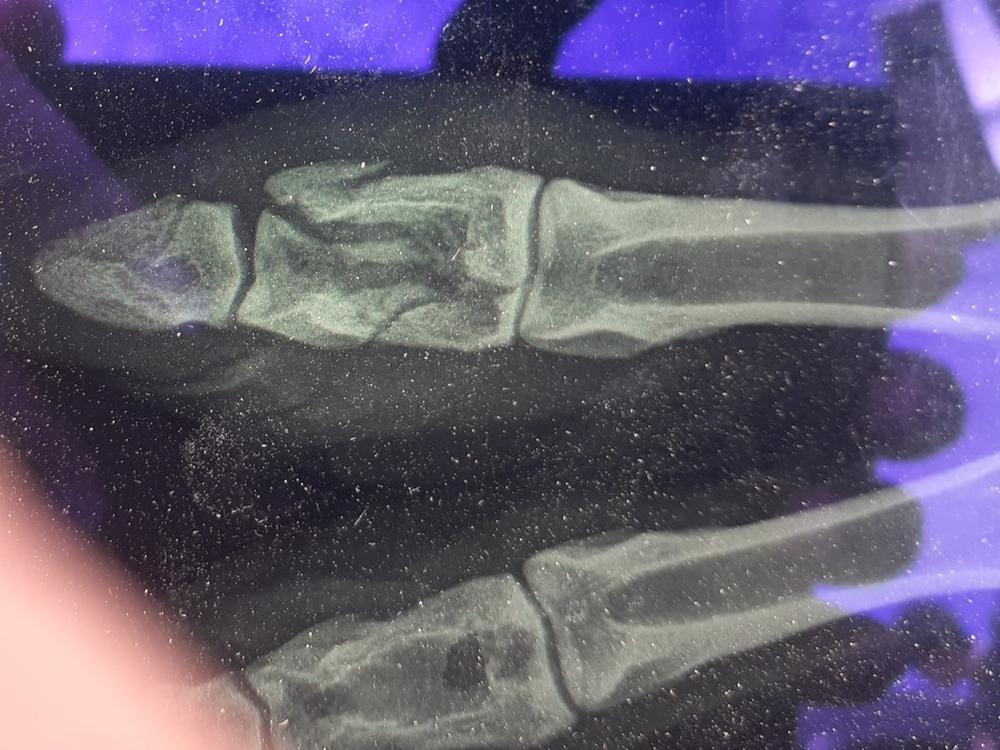

2 weeks ago I noticed Moccachino, one of my boy llamas sitting down. I wasn't very happy to see a pile of poop by his tail - llamas are very clean animals, and he had a lovely poop pile where he would normally have gone. I managed to get him to stand, and discovered he was totally lame on his front left foot. The vet came out first thing to have a look at him, and was confident that it wasn't an upper leg injury. She could find no swelling, his joints moved freely without pain, even his foot seemed OK. Or was it? She thought she could detect a little heat. So maybe he had a sprain? So she gave him a pain killer and antibiotics, just in case she had missed a wee wound, and advised rest. The waitress service kicked in - three times a day he received a big pile of hay and a bucket of fresh water, placed carefully in front of him so he didn't scare, and he was the model patient. He got up to poop, moved a little way away and sat again. A week later no change, so the vet came back. This time we decided that the best thing to do was get an x-ray and just make sure it was nothing more sinister than a sprain. So the following day two vets attended, and x-rays were taken in the paddock. Wow, he had broken a toe, spectacularly, in 5 places. How is a total enigma, as he lives alone in one of our stud paddocks, but broken it was. The treatment? Rest, so the waitress service continues, the vet is checking it regularly and is pleased with his progress (he is able to get up and down using his knee, so is resting the foot totally, clever boy.) In the meantime I have unexpected vets bills to pay, which is sucking up my winter hay savings, as well as the hay bill for his waitress service (as well as being down to my last 10 bales, so need to buy some more in over the next week or two.)